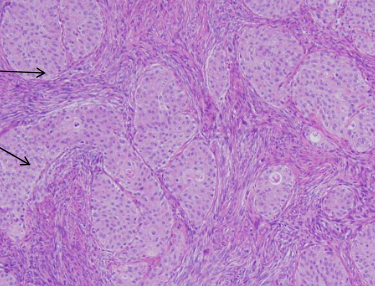

brenner tumor histology

usually unilaeral, solid

nests of transitonal type epithelium

mostly benign